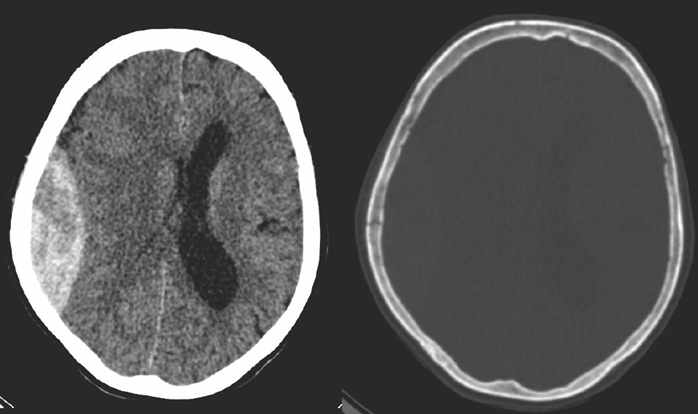

4.Middle-aged man some days after direct head trauma. On noncontrast CT a lens-shaped, slightly inhomogenous epidural hematoma can be seen, that causes compression of the right lateral ventricle (left panel). In bone window skull fracture without dislocation can be found at the site of the hematoma (right panel).